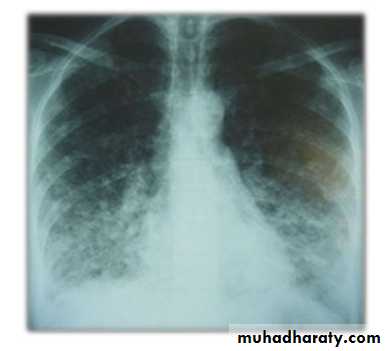

Q7/ A 13-year-old develops fever, malaise, sore throat, and a dry, hacking cough over several days. He does not appear to be particularly sick, His chest examination is reveal rales and rhonchi. The chest radiograph is shown below.

• What is the most likely diagnosis and most likely causative pathogen?

The radiograph shown has reticulonodular opacities in the right upper lobe and prominence of the right hilum (lymphadenopathy) consistent with M pneumoniae.

NOTE: Infections with M pneumoniae are common in older children and young adults. Although the infection typically produces an interstitial infiltrate, its effects are characteristically nonspecific, and it can produce lobar pneumonia as well. It can produce upper respiratory infection, pharyngitis, otitis media and externa, bronchiolitis, hemolytic anemia, and Guillain-Barré syndrome. Treatment of choice is a macrolide antibiotic.